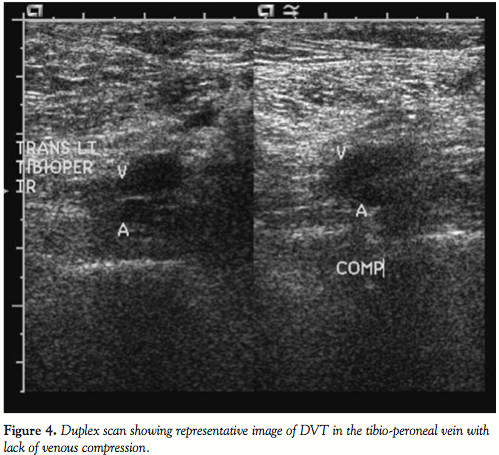

Fifty mg of alteplase was administered as a bolus through the right subclavian central venous line. In less than 60 minutes, the patient’s blood pressure improved remarkably and within 2 hours he was weaned off all vasopressors. The ECG showed normal sinus rhythm (atrial fibrillation resolved) and the RBBB became partial RBBB after 90 minutes (Figure 2). Partial RBBB resolved completely by the next day (Figure 3). The patient was extubated the following day. A Doppler ultrasound of lower extremities was performed, which showed thrombus in bilateral tibial and peroneal veins and right popliteal vein (Figure 4). He was continued on enoxaparin and then warfarin. Within the week, the patient recovered completely and was discharged with plan for long-term anticoagulation.